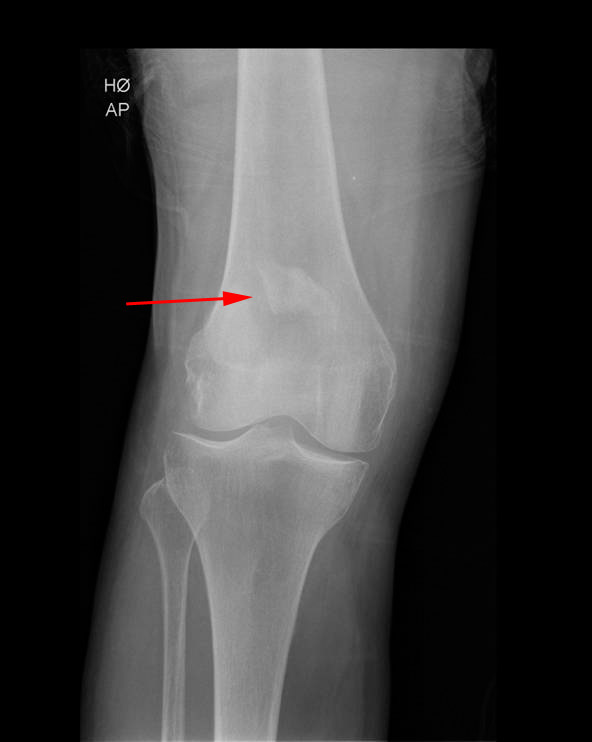

Røntgenbillederne nedenfor viser brud på knæskal set forfra og fra siden:

Brud på knæskal, røntgenbillede

For at se om der er brud, og eventuelt hvor bruddet er, bliver der taget røntgenbilleder af knæet. På billedet skelner man mellem forskudte eller ikke forskudte brud, og mellem længdegående brud, tværgående brud, afrivningsbrud eller knusningsbrud.